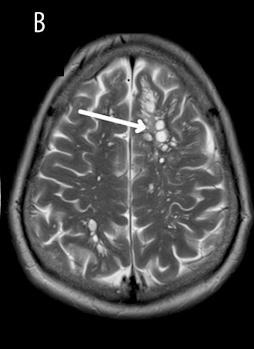

Zum Zeitpunkt der Erstvorstellung im Krankenhaus zeigten die Vitalwerte des Patienten keine Auffälligkeiten – so auch die neurologische Untersuchung. Aufgrund der besorgniserregenden und anhaltenden Veränderung der Migräneanfälle des Patienten wurde zunächst eine CT-Untersuchung durchgeführt und im Anschluss ein MRT des Gehirns. Die Bildgebung ergab folgende Befunde:1

Bildabschnitt B: Im MRT des Gehirns waren multilokuläre zystische Läsionen im frontalen und parietalen Kortex (weißer Pfeil) erkennbar gewesen.1